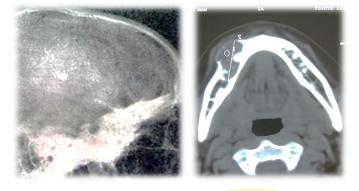

骨化性纤维瘤是一种良性肿瘤,多发生于青年人,常为单发性,以下颌骨为多见。在X线片上表现为颌骨局限性膨胀,病变向四周发展,界限清楚,圆形或卵圆形,密度减低,病变内可见不等量的和不规则的钙化阴影。骨纤维异样增殖症则为发育畸形,发病年龄较早,病期较长,以上颌骨为多见,常为多发性。在X线片上表现为颌面骨广泛性或局限性沿骨长轴方向发展,呈不同程度的弥散性膨胀,病变与正常骨之间无明显界限。其密度根据病变中含骨量多少而异,有的呈密度高低不等阴影,有的呈毛玻璃状,少数表现为多房性囊状阴影。

以下附上两张临床的X线片,给大家作参考: